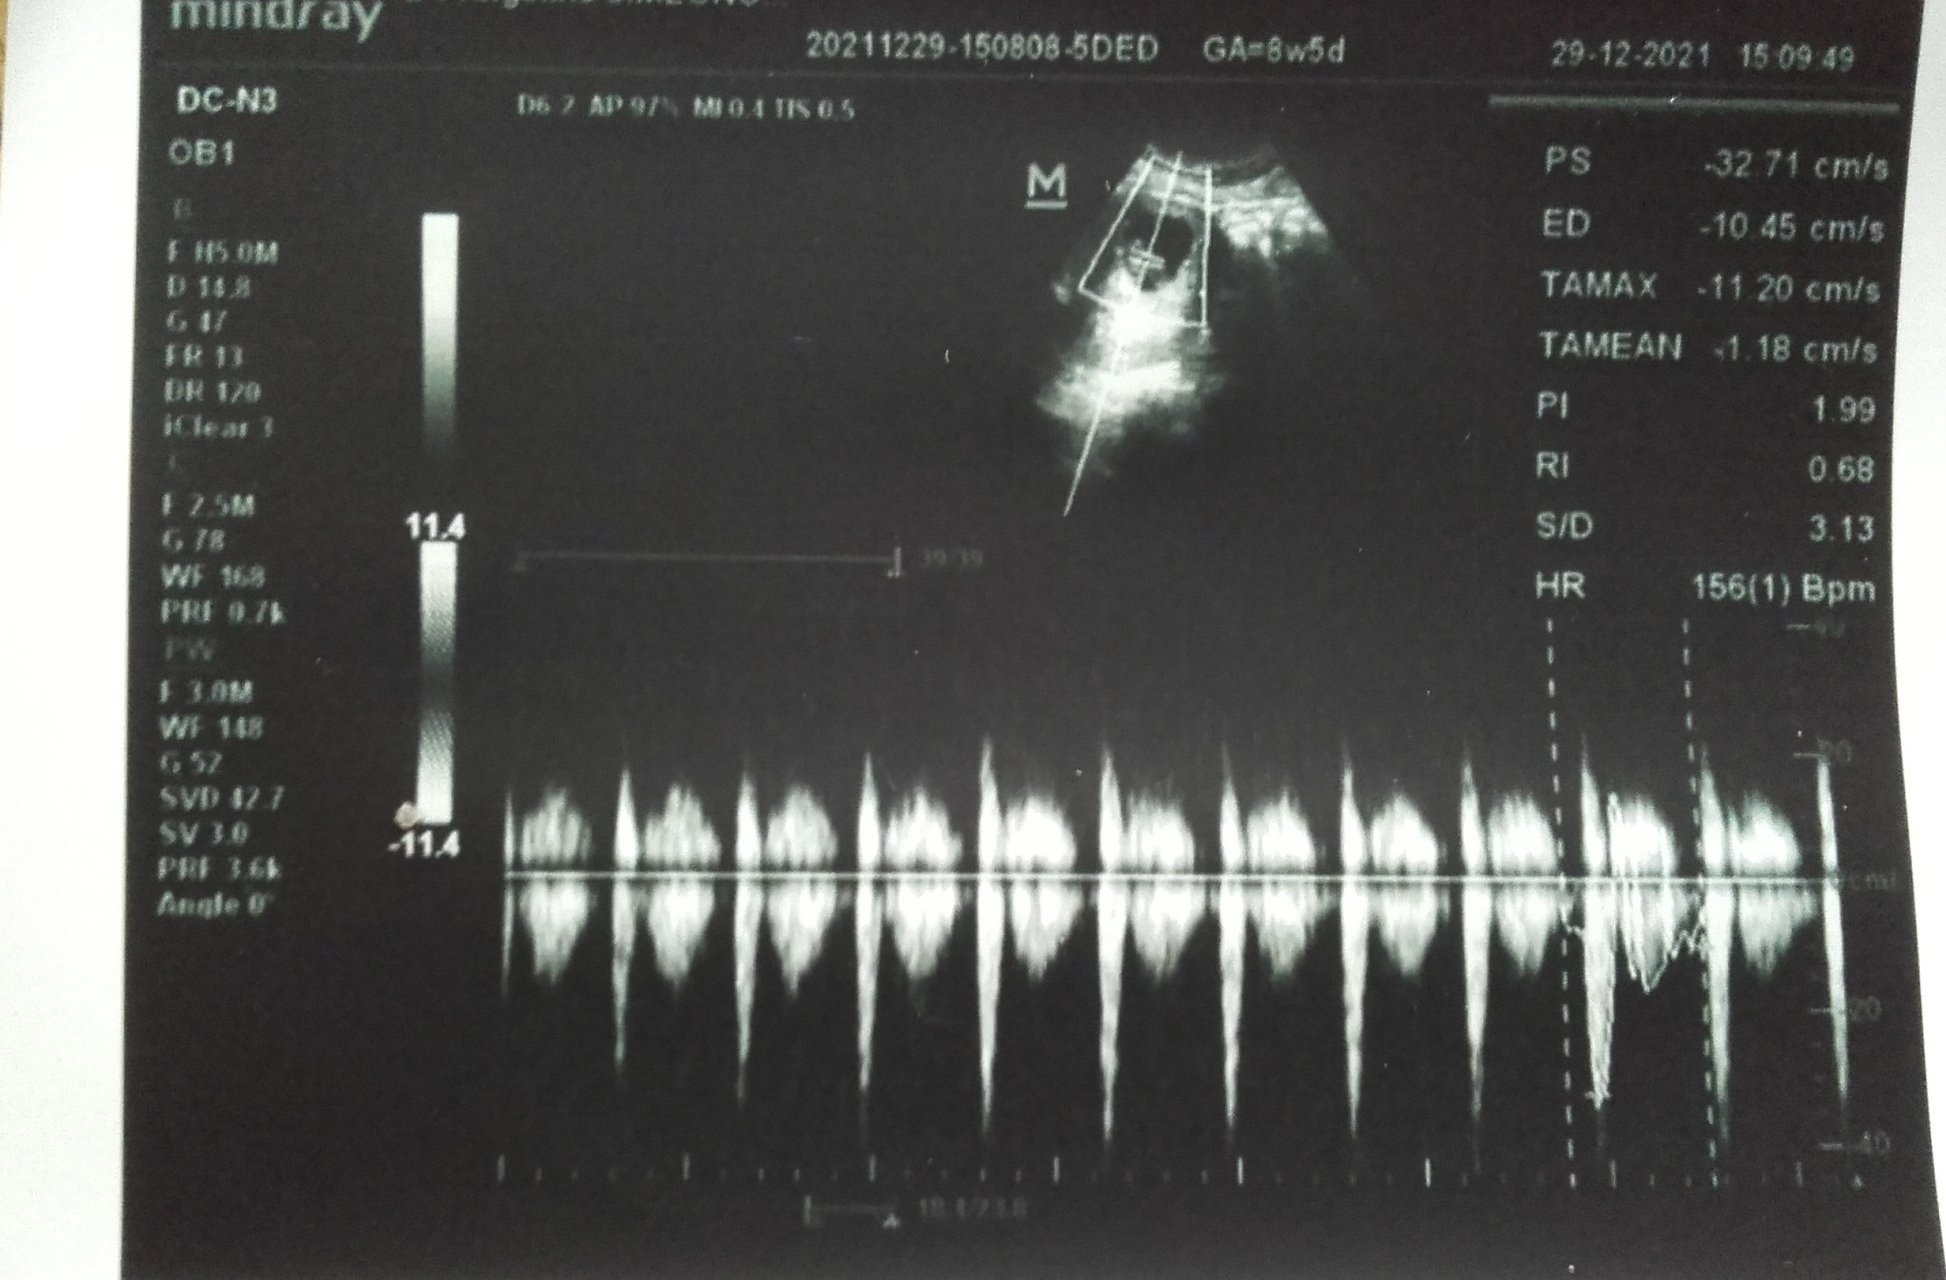

Как се наблюдава както тромбофилията, така и кръвният поток по време на бременност?